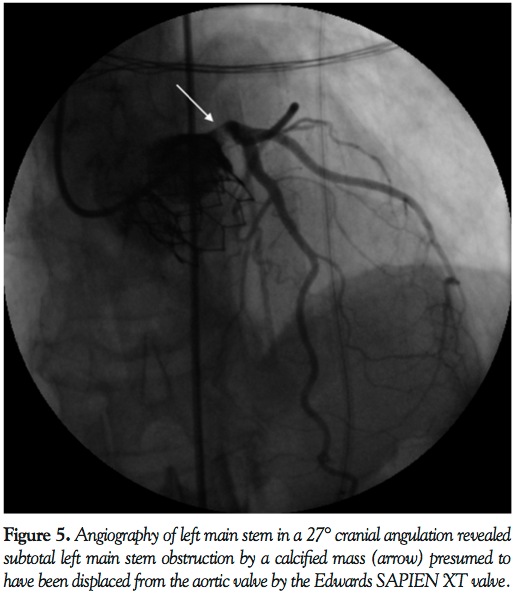

PCI was planned. To facilitate transfer and angiography, CPR using an automated load distributing chest compression device (Autopulse, Zoll Circulation) was commenced. The patient was emergently intubated and transported to the catheter laboratory. The AutoPulse gave excellent hemodynamic support (Figure 4) as compared with no support, assessed by invasive arterial pressure monitoring, and allowed uninterrupted CPR during transfer to the catheter laboratory table. Coronary angiography revealed subtotal occlusion of the LMS by a calcified mass with TIMI 2 flow (Figure 5). During automated chest compressions with AutoPulse, angioplasty guidewires were positioned in the left anterior descending and circumflex arteries and after predilatation with a 2.5 mm x 15 mm compliant balloon the LMS was stented with a 4 mm x 12 mm Integrity Resolute device (Medtronic) (Figure 6). This immediately restored TIMI 3 flow in the left coronary artery and was followed by return of spontaneous circulation, allowing removal of the AutoPulse. The total period of cardiac support with AutoPulse was 38 minutes. Intravascular ultrasound (Boston Scientific) revealed a calcified mass indenting the stent lumen at the mid and proximal section. Postdilatation with a 5 mm non-compliant balloon led to improvement in the angiographic appearance of the stent. Repeat intravascular ultrasound examination demonstrated improvement in minimum lumen area and diameter, but mild residual indentation at the site of the